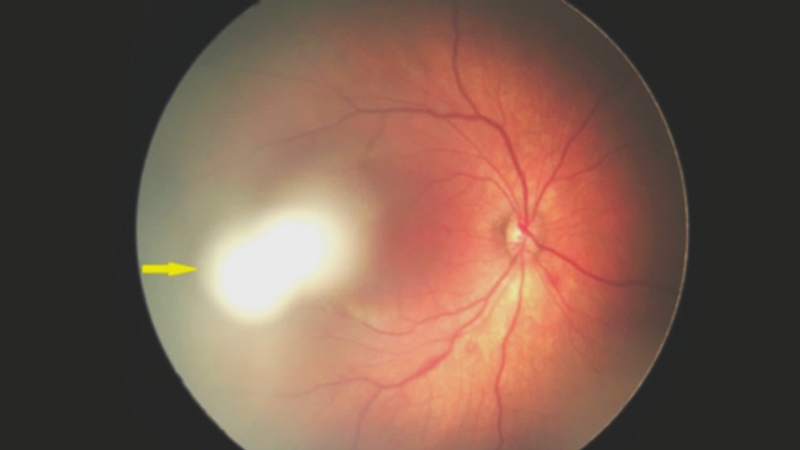

2. Frühgeborenen-Retinopathie

Frühgeborenen-Retinopathie (ROP) ist eine Netzhauterkrankung, die vor Termin geborene Säuglinge betreffen kann. Die Netzhaut wird bei diesen Frühgeborenen nicht vollständig ausgebildet und eine abnormale Entwicklung schwacher Netzhaut-Blutgefäße kann zu Sehbehinderungen führen.

Nach Angaben des National Eye Institute sind in den USA jedes Jahr 14.000 bis 16.000 Säuglinge in bestimmtem Maße von ROP betroffen. Etwa 90 % dieser Fälle werden als leicht eingestuft und diese Säuglinge benötigen bei Besserung der Krankheit keine Behandlung.

In schweren Fällen entwickeln die Säuglinge jedoch möglicherweise eine Netzhautablösung (Bild 3), bei der sich die Netzhaut von der Schicht der Blutgefäße trennt, die die Netzhaut mit Sauerstoff und Nährstoffen versorgt. Unbehandelt kann dieser Zustand zur Erblindung führen. Aus diesem Grund werden Frühchen in der NICU von Krankenhäusern sorgfältig auf ROP untersucht.9

Es besteht Ungewissheit darüber, wodurch eine ROP verursacht wird. Ein geringes Geburtsgewicht und wie früh ein Baby geboren wird gelten jedoch als Faktoren, die das ROP-Risiko erhöhen. Wenn ein Baby zum Termin geboren wird, ist das Wachstum der Blutgefäße weitgehend abgeschlossen, da sich die Netzhaut einige Wochen bis zu einem Monat vor der Geburt vollständig ausgebildet hat. Wenn ein Baby vor Termin geboren wird und die Blutgefäße die Ränder der Netzhaut noch nicht erreicht haben, wird die normale Gefäßbildung möglicherweise unterbrochen.10

In schweren Fällen von ROP entwickeln Säuglinge möglicherweise sichtbare Symptome wie Leukokorie, Nystagmus (abnormale Augenbewegungen) und Strabismus (Schielen). Da die meisten Anzeichen einer ROP jedoch tief im Inneren der Augen auftreten, sind diese nicht leicht erkennbar und können gewöhnlich nur von einem Ophthalmologen festgestellt werden, der die Netzhaut des Babys untersucht.11